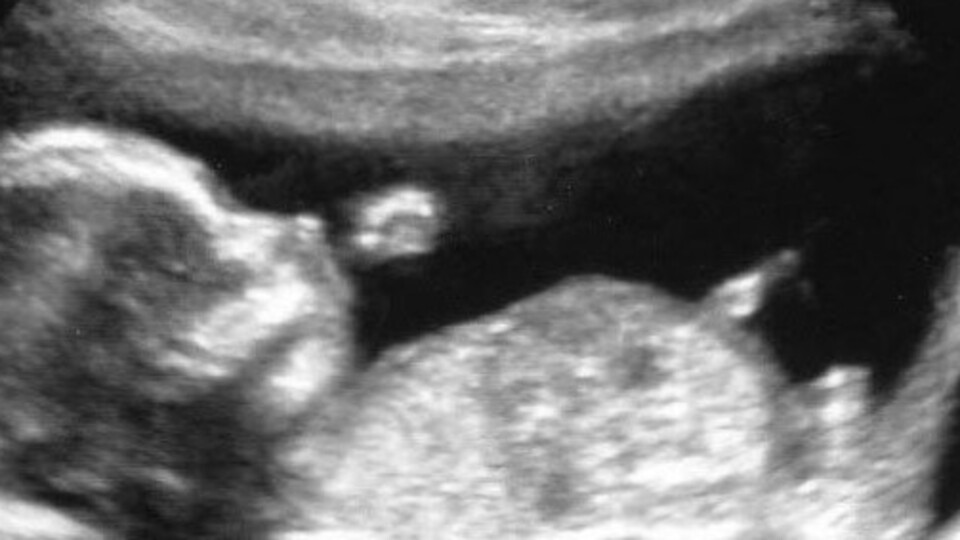

Bebeğiniz bu haftadan itibaren solunum yapma çalışmalarına hız verir. Gözler ve kulaklar gelişimini sürdürmekte, boyun uzamaktadır. Bebeğin başı daha da hareketlenmiş ve çenesine yaslanmış sabit pozisyonundan kurtulmuştur. Bebeğiniz artık ellerini ve ayaklarını kendi isteğine göre serbestçe hareket ettirmektedir.

Bu hafta sonunda bebeğinizin boyu 10 cm. ve ağırlığı tam 45 gram!